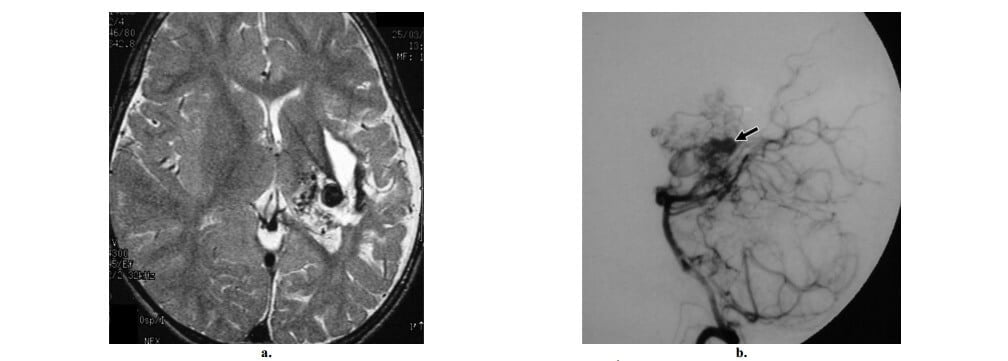

Nếu có một nidus, có thể gặp hai phân nhóm mạng lưới mạch máu bất thường. Kiểu thông thường là nidus kiểu hình cầu hay kiểu đặc, gồm các mạch máu bất thường mà không có bất kỳ một nhu mô não bình thường nào xen vào (hình 2, 3). Kiểu thứ hai hiếm gặp hơn, còn gọi là nidus kiểu tăng sinh hay lan tỏa, trong đó nhu mô não bình thường xen vào khắp đám rối mạch máu (hình 4). Nếu có dấu hiệu này, bệnh mạch máu tăng sinh hoặc hội chứng phân đoạn động-tĩnh mạch não-mặt (CAMS) cần phải đưa vào trong chẩn đoán phân biệt và có thể phân biệt với AVM não thực sự dựa vào sự vắng mặt của dẫn lưu tĩnh mạch sớm thấy trong bệnh mạch máu tăng sinh, vị trí kinh điển và đi kèm AVM mặt gặp trong CAMS.

Hình 2: AVM não kiểu nông kinh điển ở bệnh nhân nam 18 tuổi có máu tụ vùng đính trái. (a) Axial cản quang cho thấy một đám rối cấu trúc dạng ống bắt quang mạnh nhúng trong thùy đính trái, một dấu hiệu hợp với nidus. Ghi nhận tăng đậm độ biểu hiện xuất huyết trong não thất. (b) Hình ảnh hướng cường độ tối đa (MIP) (nhì từ đáy) từ dữ liệu chụp mạch CT cho thấy lớn động mạch não giữa trái (so với bên phải), cấp máu cho nidus. (c) Chụp động mạch cảnh trong trái thế nghiêng thấy một nidus kiểu hình cầu ở vị trí vỏ não, được cấp máu chủ yếu bởi nhánh góc và nhánh đính sau của động mạch não giữa trái, với dẫn lưu sớm vào tĩnh mạch vỏ đính trái, các dấu hiệu khẳng định chẩn đoán AVM não.

Hình 3: AVM não kiểu sâu kinh điển ở bệnh nhân nữ 19 tuổi đau đầu đột ngột sau đó mất tri giác. Khám thực thể thấy liệt dây thần kinh VI hai bên. (a, b) Axial CT không cản quang (a) và cản quang (b) các cấu trúc mạch máu bắt quang mạnh ở đồi thị trái. Mặt dù không có bằng chứng xuất huyết trên CT, lâm sàng có nghi ngờ hiều đến vỡ. (c) Chụp động mạch cột sống trái thế nghiêng giúp khẳng định sự hiện diện của AVM đồi thị, được cấp máu bởi động mạch xuyên đồi thị và các nhánh động mạch mạch mạc sau trái và dẫn lưu chủ yếu vào tĩnh mạch Galen và dẫn lưu ít vào tĩnh mạch nền của Rosenthal bên trái (mũi tên). Ghi nhận các túi tĩnh mạch nhỏ (đầu mũi tên), sự hiệndiện của các túi này gợi ý nguy cơ xuất huyết cao.